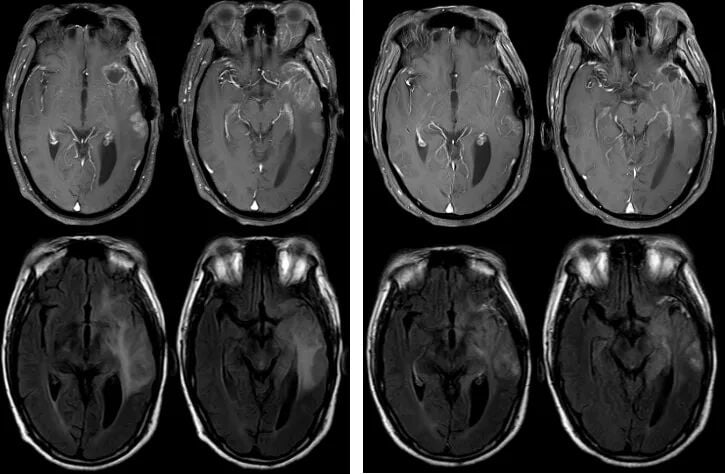

图4. 再次复发后的影像学检查结果

2023年7月,在多线治疗失败、肿瘤再次增大的困境下,医生决定采用一种新的挽救治疗方案:替尼泊苷化疗(100mg d1-3, q3w)联合贝伐珠单抗靶向治疗(400mg q3w)。

令人振奋的是,仅仅经过两个周期的治疗,2023年9月的复查MRI便显示,肿瘤强化范围较前略有缩小,疗效评估为疾病稳定(SD)。这意味着新方案有效遏制了肿瘤的生长。截至2023年12月,经过5个周期的治疗,患者病情持续稳定。

图5. 替尼泊苷联合贝伐珠单抗治疗后,病灶得到有效控制